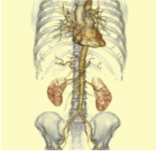

大動脈VR -

下肢動脈VR -

下肢動脈MIP -

下肢動脈拡大VR